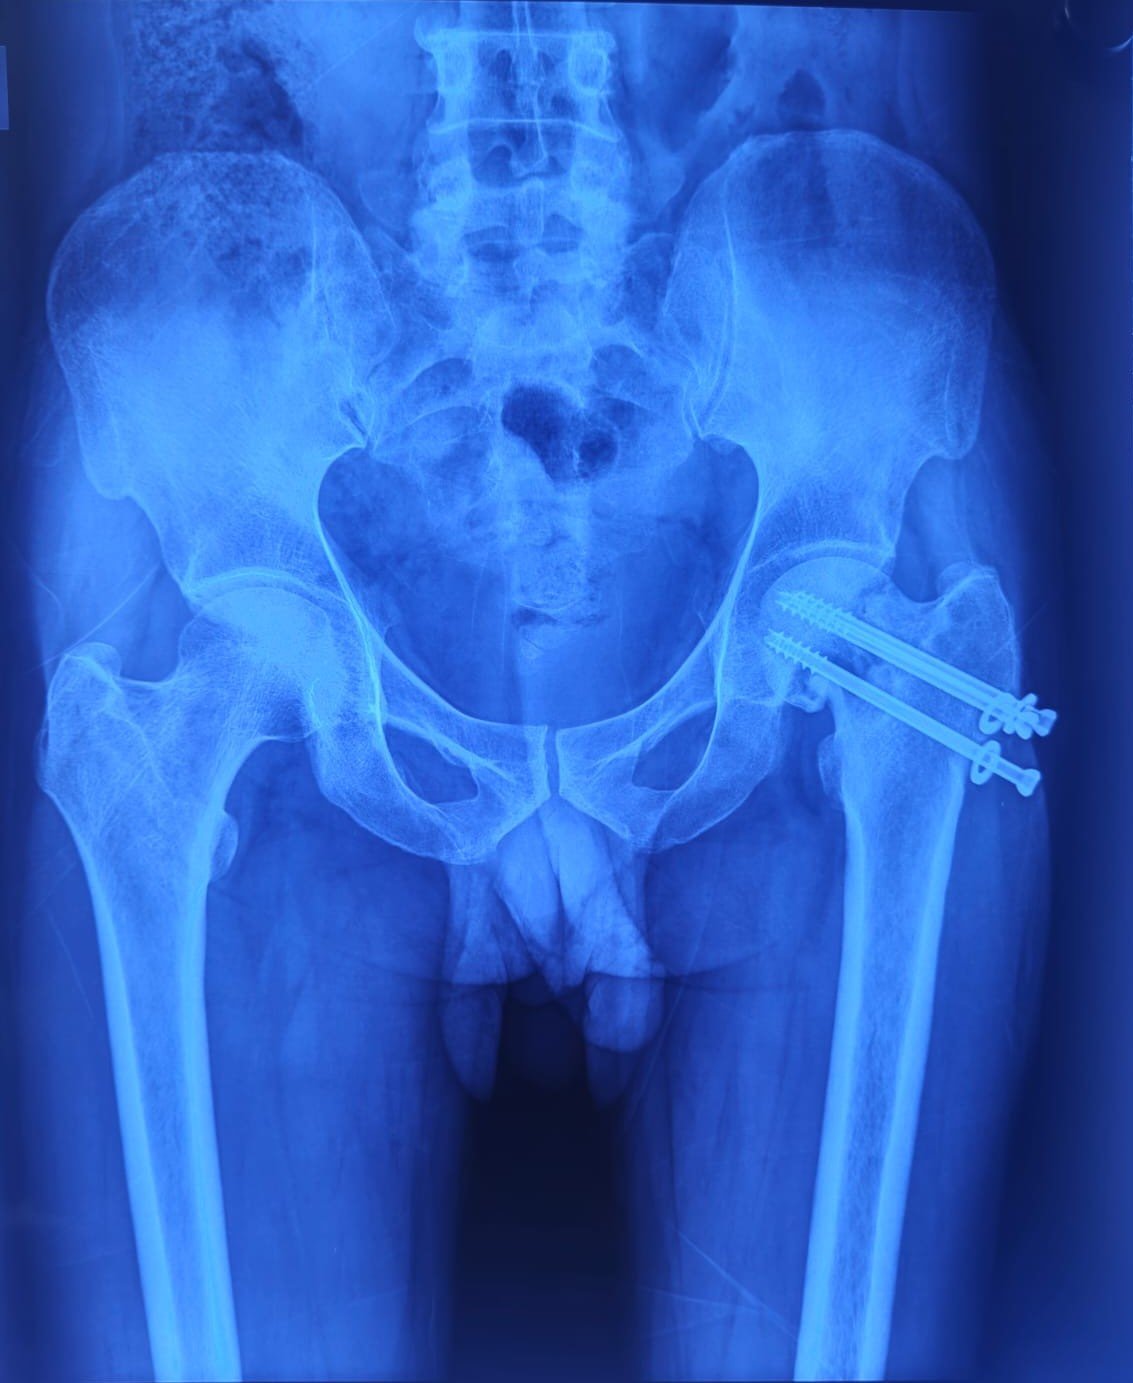

Pre-Op X-Ray

Non Union & Fixation Failure Post CHS